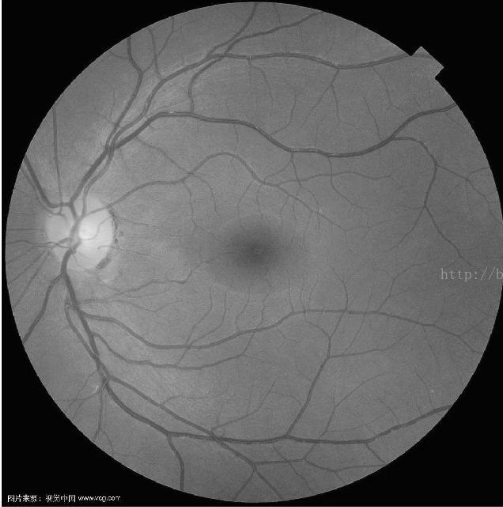

那一副醫學圖像做測試,效果確實不錯:

原圖 尺度數量為5,最大尺度為16的結果

同樣參數原始作者版本的結果,明顯沒有maltab的清晰

這個算法我測試確實對血管圖像的提取效果比較顯著,在貼幾個圖片。